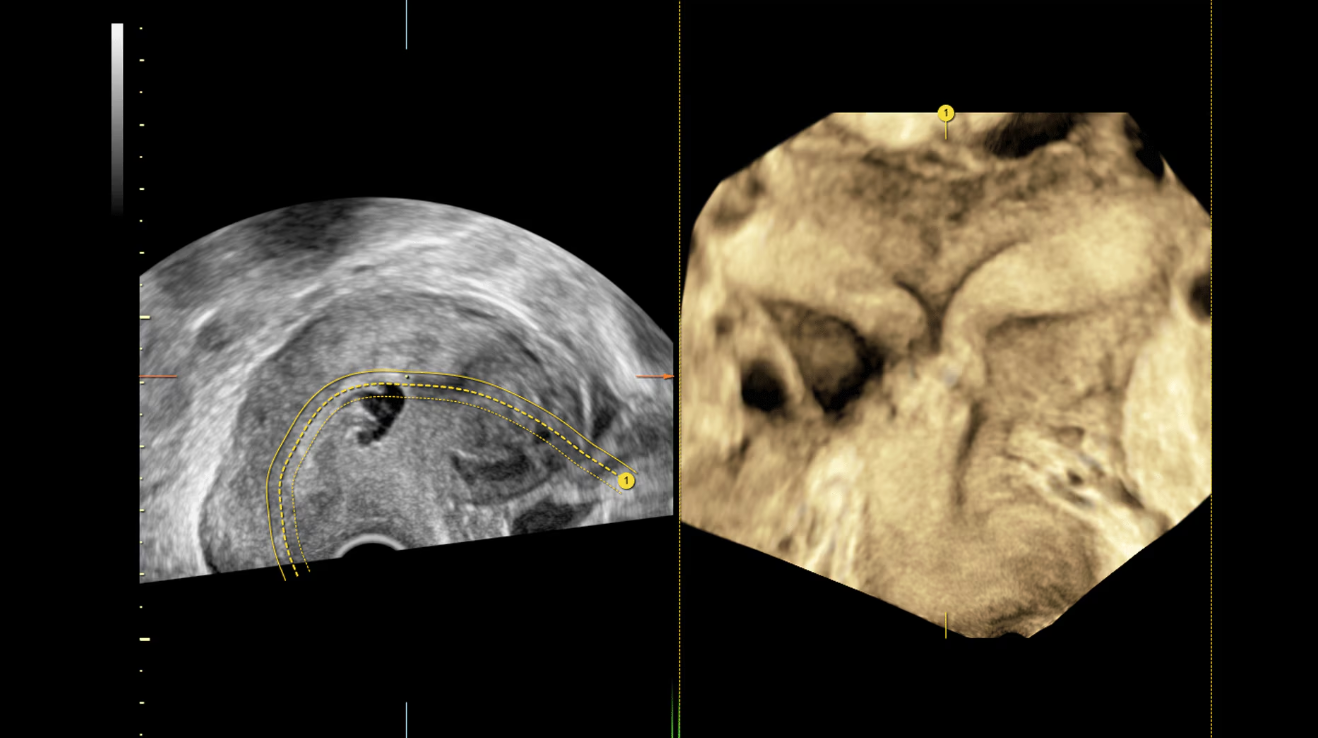

Матка с перегородкой, визуализированная с помощью Uterine Trace